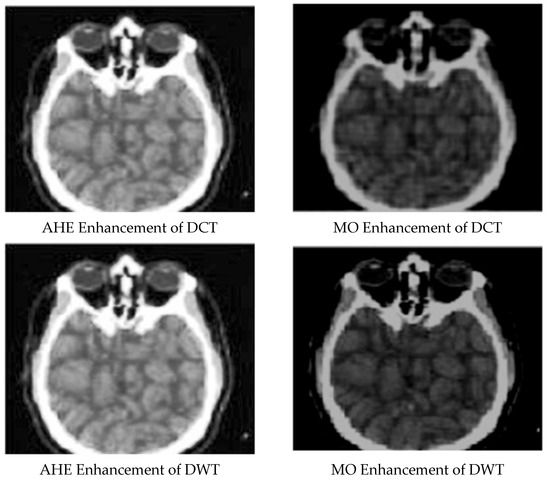

Enhanced and Compressed Output

| 1 | DCT compressed Image | 0.976102286 | 4.15 × 10−5 | 89.97979612 |

| 2 | AHE enhancement for DCT compressed image | 0.953323544 | 0.01256723 | 82.67223261 |

| 3 | DWT compressed image | 0.060732271 | 0.555070285 | 54.76541543 |

| 4 | AHE enhancement for DWT compressed image | 0.996540627 | 4.14 × 10−5 | 86.98046733 |

| 5 | MO enhancement for DWT compressed image | 0.919275875 | 0.012887986 | 72.76504215 |